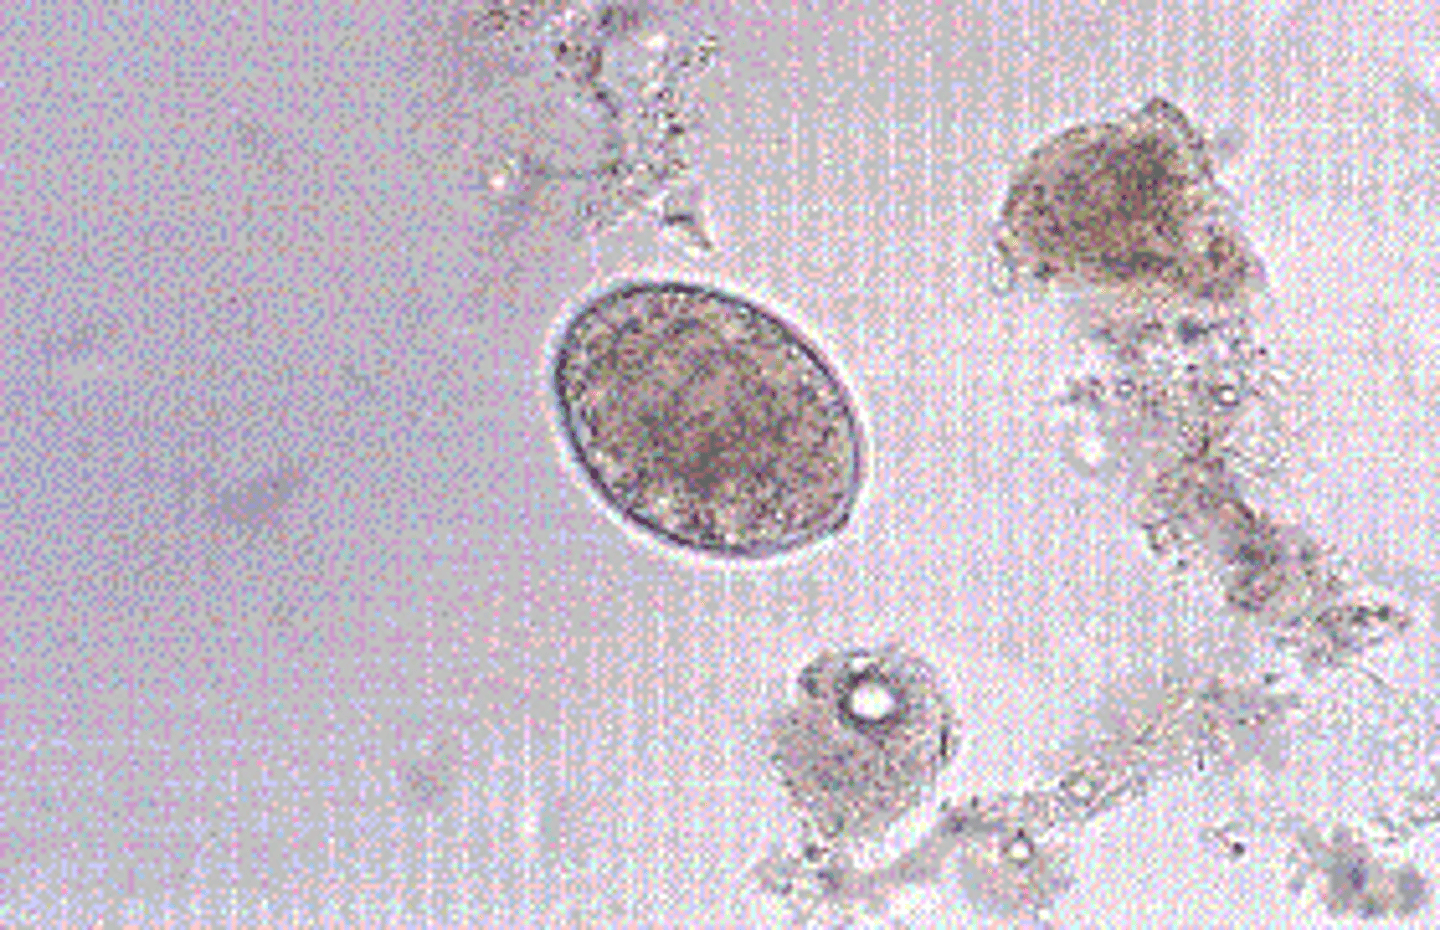

A 4-year-old child has been complaining of a stomachache and has had intermittent episodes of diarrhea. Physical examination reveals an apparently healthy child with a mildly distended abdomen. Because of the diarrhea, a fecal sample is sent for culture and for ova and parasites examination. What is the identity of that found at 400× in the child’s fecal sample?

a.Ascaris lumbricoides

The usual diagnostic stage is the egg. Fertile Ascaris eggs are oval, measure 45 to 75 μm by 35 to 50 μm, and have thick hyaline walls surrounding a one-cell-stage embryo. Most eggs have a brown, bile-stained mammillated outer layer, not seen in this image